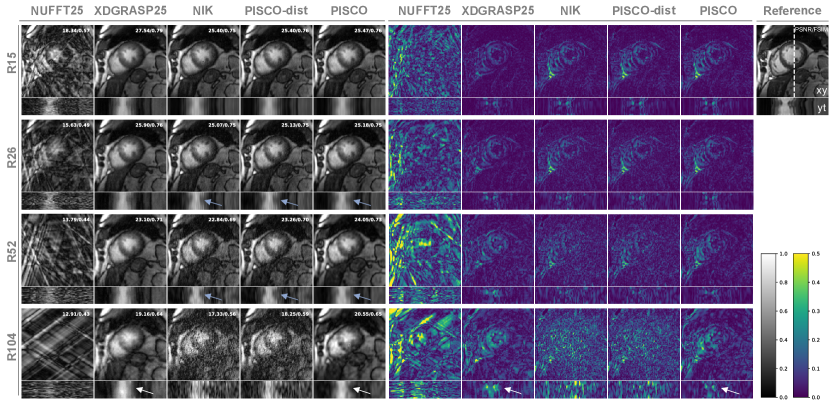

Cardiac Cine Quantitative results of the cardiac cine dataset (Fig. 5) show that PISCO consistently outperforms NIK and PISCO-dist at all acceleration factors in both, spatial and temporal metrics. Particularly at high acceleration factors (R52/R104 or 4/2 spokes per frame), NIK’s and PISCO-dist’s spatial and temporal performance drastically decay. In contrast, PISCO enables spatial reconstruction quality similar or better to the reference method XD-GRASP25 (PSNR/FSIM-spat) and additionally, models the temporal dynamics better at these high accelerations (FSIM-temp).

Similar observations can be made in the qualitative reconstructions of one exemplary subject (Fig. 6). All motion-resolved reconstruction methods, XD-GRASP25, NIK, PISCO-dist and PISCO, encounter the strong undersampling artefacts visible in INUFFT. XD-GRASP results in spatial smoothness by regularizing over the temporal dimension, which introduces blurring, particularly with reduced data (R52/R104). NIK and PISCO-dist result in noisy spatiotemporal reconstructions, particularly with increasing acceleration factors. With PISCO, an improved neural k-space representation could be learned, that is spatially smooth, and recovers temporal dynamics even at 2 spokes/frame (R104). At high acceleration rates (R52/R104), PISCO surpasses the state-of-the-art XD-GRASP25 in capturing temporal detail (FSIM-temp) while achieving comparable spatial smoothness (PSNR/FSIM-spat). Note that in this case, only 25 time points were analyzed due to the use of binned reference data. Yet, PISCO’s temporal resolution can further be increased by sampling more temporal points. Nonetheless, at accelerations like R104, the resulting images do not yet reach diagnostic quality but may be valuable for intermediate applications, such as motion estimation.